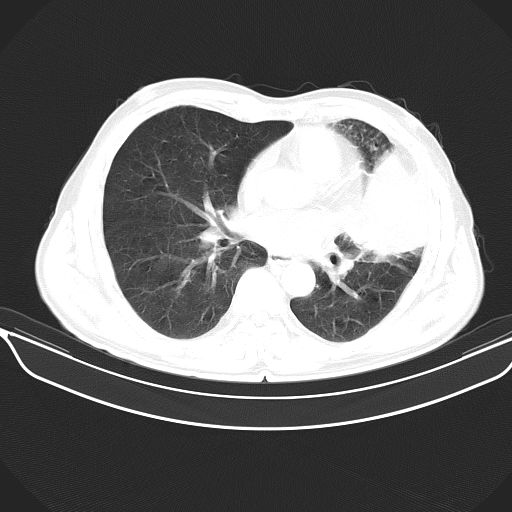

以下是引用心路寻觅在2010-3-1 10:23:00的发言:[br]1、考虑左肺上叶周围型肺癌[br]2、右上肺陈旧性病灶。[br][br][本贴已被 心路寻觅 于 2010-3-1 10:40:18 修改过]

以下是引用shuiyuan在2010-3-1 10:45:00的发言:[br]考虑左肺上叶中心型肺癌伴阻塞型炎症,邻近胸膜受侵。